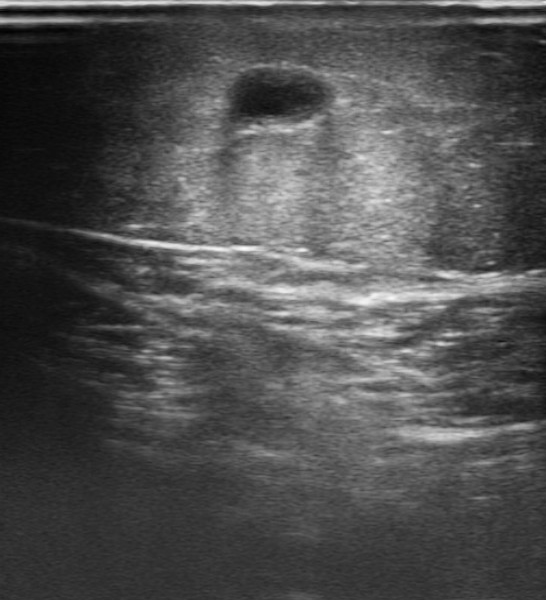

Ecografía de miembro inferior izquierdo: contenido hiperecogénico en todo el trayecto de la vena safena interna, no compresible. Sistema venoso profundo permeable sin datos de TVP (Imagen 2,3,4).